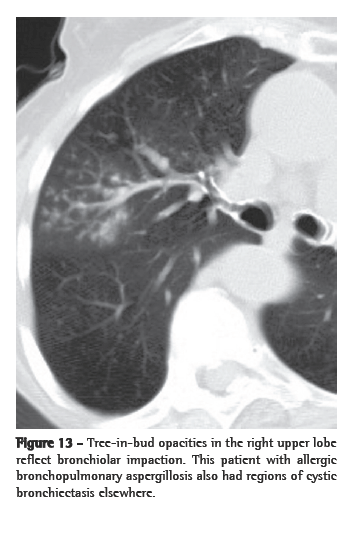

The central part of the secondary pulmonary lobule contains the branches of the terminal bronchioles, their accompanying pulmonary arteries, and, adjacent to them, supporting connective tissue with lymph vessels. Therefore, centrilobular nodular opacities can result from bronchiolar and peribronchiolar diseases, as well as from vascular and perivascular diseases. Mosaic attenuation associated with air trapping on expiratory HRCT, or functional evidence of airflow obstruction indicates diseases involving the peripheral airways. Centrilobular nodules are sometimes accompanied by the so-called "tree-in-bud" opacities, in which the abnormality resembles a budding tree. In the majority of cases, the tree-in-bud pattern occurs as a result of infectious diseases. Tree-in-bud is a subtype of a centrilobular pattern. Pathologically, this abnormality represents bronchiolar impaction and is almost always due to infection. The differential diagnosis is detailed in Chart 7.

Infectious pneumonia

In the immunocompromised host, bacterial (Staphylococcus aureus and

Haemophilus influenzae), fungal (more commonly Aspergillus spp.) and, quite rarely, viral infection can all result in a tree-in-bud pattern (Figure 13) accompanied by variable consolidation (including cytomegalovirus and respiratory syncytial virus).(55)